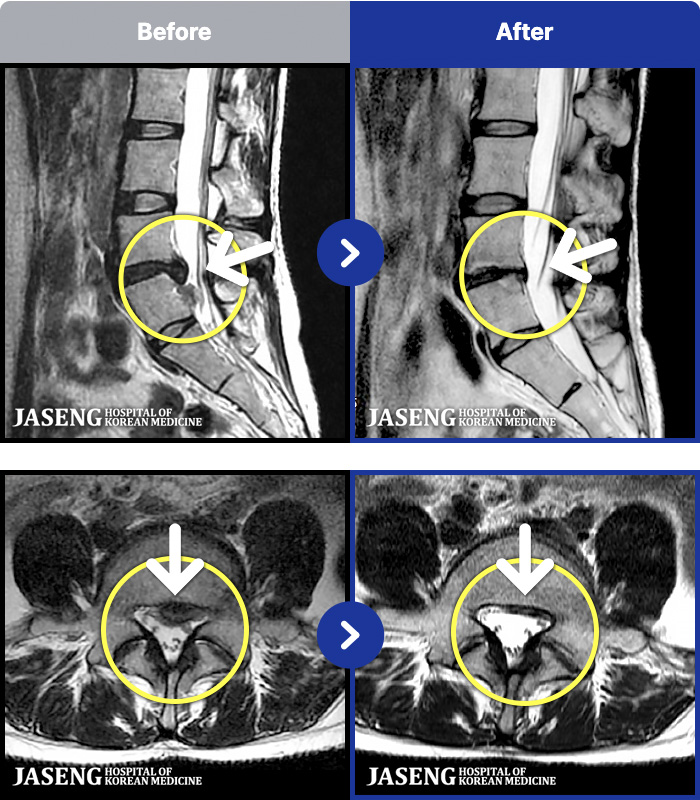

MRI ġ

MRI ũ ʸ Ȯϼ.